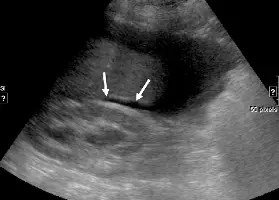

這是一張右上腹 (Right Upper Quadrant, RUQ) 的灰階超音波影像,主要呈現以下特徵:

- Liver (肝臟): 影像左側與上方佔據大部分視野、呈現均勻中等回音 (medium echogenicity) 的實質器官為肝臟右葉。

- Right kidney (右腎): 位於肝臟的後下方(影像的下半部),呈現橢圓形結構,外層皮質回音較低,內部的腎竇 (renal sinus) 則呈現明顯的強回音 (hyperechoic)。

- 箭頭所指處: 兩個白色箭頭明確指向肝臟下緣與右腎上極之間的高回音交界面,此處即為解剖學上的潛在空間。

- 周邊發現: 影像右側可見大片無回音 (anechoic) 的黑色區域,代表有游離積液 (free fluid) 累積在肝臟下緣周邊,並延伸進入前述的潛在空間中。